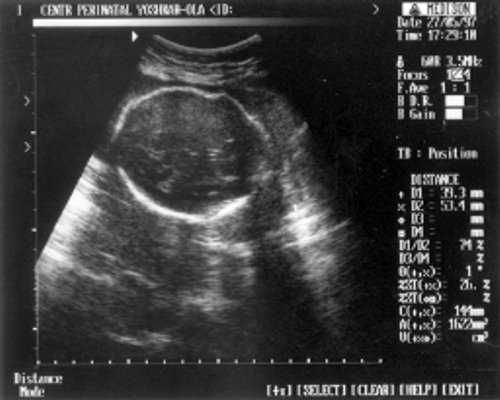

- (бипатериальный размер головы - от виска до виска) = 65 мм - 26 нед.,

- ОкГ (окружность головы) = 244 - 26 нед. + 3 дня.

- МРМ (межполушарный размер мозжечка) = 25,6 мм - 23,5-24 нед. (рис. 1)

Рис. 1. УЗИ плода - голова.